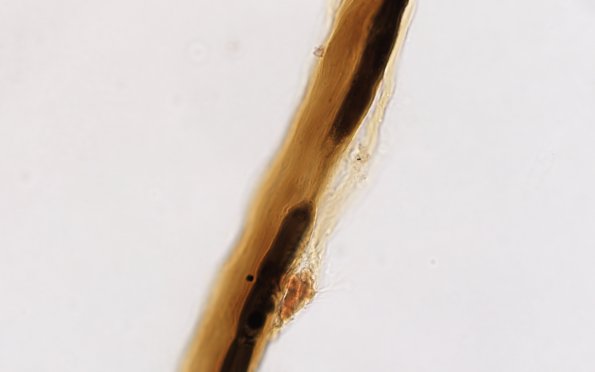

Retraction of Schwann cell processes with resultant widening of the nodal gap is considered an early change in demyelination. (Teased fiber preparation)